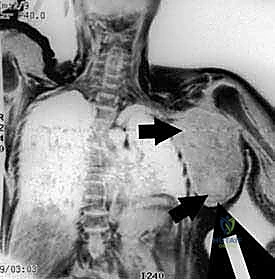

- التصوير بالرنين المغناطيسي (MRI) بالصبغة: الفحص الأهم على الإطلاق. يحدد بدقة متناهية حجم الورم، امتداده داخل النخاع العظمي، وعلاقته بالأعصاب والأوعية الدموية.

- التصوير المقطعي المحوسب (CT Scan): للصدر والبطن للتأكد من عدم وجود انتشار (نقائل) للورم في الرئتين أو أعضاء أخرى.

4. استئصال الورم ككتلة واحدة (En-bloc Resection)

يتم قطع العظام (العضد، الترقوة، أو لوح الكتف حسب امتداد الورم) باستخدام مناشير جراحية دقيقة. يتم استخراج الورم مغلفاً بطبقة من الأنسجة السليمة (هوامش الأمان). يتم إرسال عينات من الحواف فوراً إلى مختبر الباثولوجي أثناء العملية (Frozen Section) للتأكد من خلوها تماماً من الخلايا السرطانية.